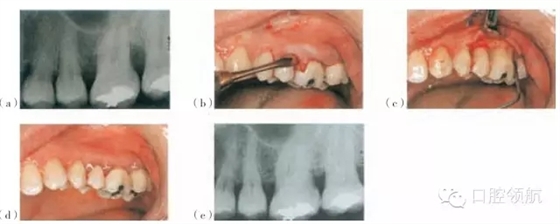

圖26.5 使用Emdogain®和PerioGlas®處理的一個病例。(a)手術(shù)位點的術(shù)前放射線圖像。(b)頰側(cè)瓣的影像。(c)使用EDTA調(diào)節(jié)器后應(yīng)用Emdogain®。(d)瓣的復(fù)位與縫合。(e)術(shù)后18個月的放射線圖像

Straumann®, Emdogain也可以被用在骨移植材料的結(jié)合處,例如作為骨沉積的支架(圖26.5)的Bio-Oss®(GeistlichPharma AG),PerioGlas®或者StraumannBoneCeramic 400-700®。Emdogain®還可以與GTR技術(shù)聯(lián)合應(yīng)用。